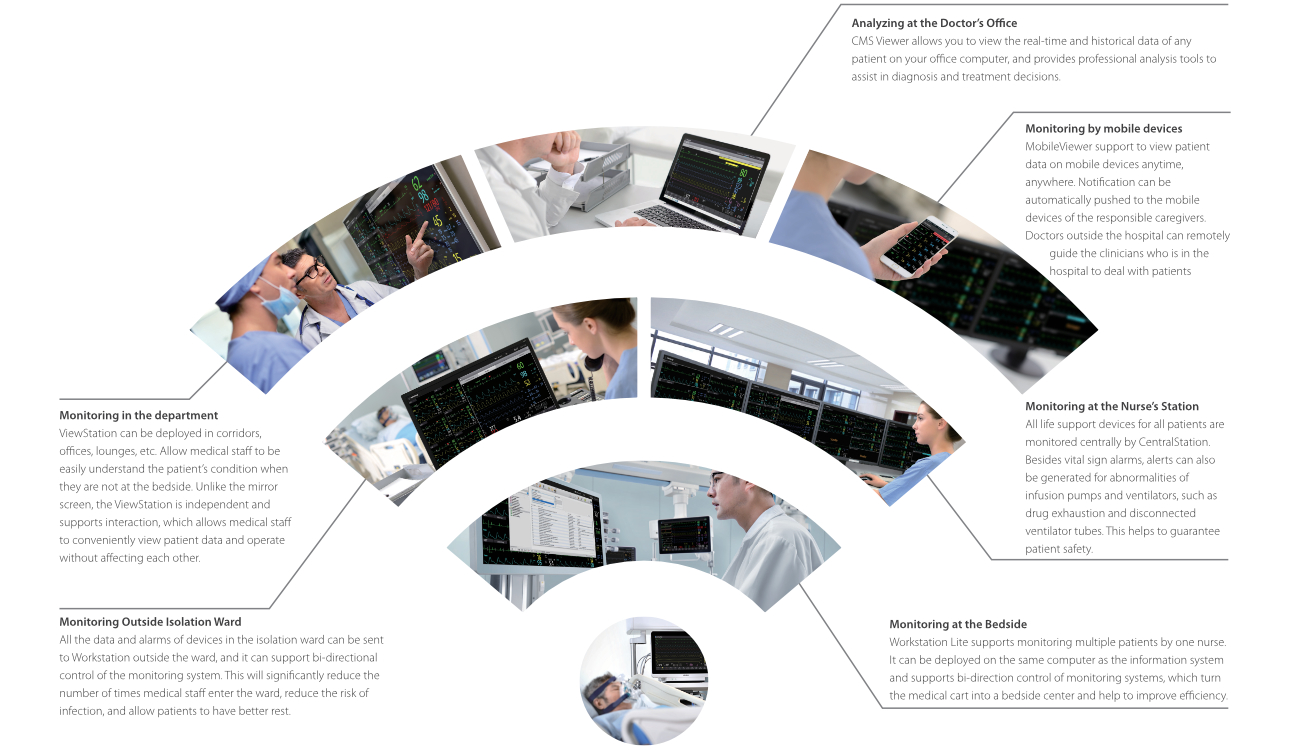

MindrayŌĆÖ s M-Connect IT Solution is a patient-centric, distributed monitoring solution integrating all bedside equipment data into the monitor to allow clinicians to access patient data including real-time and historical data at bedsides, nurse stations and doctor's offices in the hospital and even outside the hospital at any time, so as to adjust the diagnosis and treatment plans in time and assist in diagnosis and treatment.